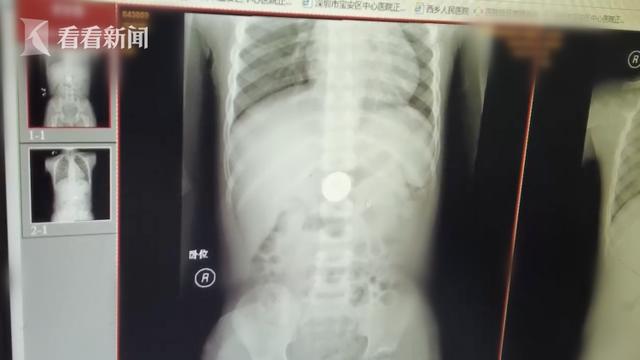

宝安区中心医院消化内科主任廖晓红告诉记者:“(硬币)躺着的时候在这个地方,站着的时候在这个地方。胃里的硬币是活动的,所以这个时候我就是下不去,硬币已经在胃里放了七天了。”由于硬币比较光滑,医生一般建议保守治疗,尽快将硬币取出体外。如果过了几天,硬币还留在消化道里不动。这意味着硬币停留的地方损伤了局部黏膜,时间长了会导致胃黏膜或肠黏膜损伤出血,甚至严重穿孔。硬币大了,胃肠道会有嵌顿和梗阻。

廖晓红说:“孩子有不适感,就是有时候会觉得恶心、呕吐、腹痛,有时候会断断续续。因为孩子太小,可能还不到七岁,这时候我们申请在手术室无痛内镜下取异物,这是常见的手术。”考虑到硬币已经在小豪的消化道停留了一周,消化内科门诊医生建议胃镜下取出异物。一般来说,成年人从消化道取出异物并不难。但对于儿童来说,如果小豪不能配合常规胃镜检查,需要在全身麻醉下进行。